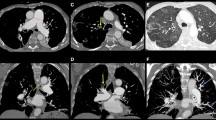

Pulmonary angiography is the gold standard for defining pulmonary vascular anatomy and is performed to confirm the diagnosis and to determine the location and surgical accessibility of thromboembolic disease. In angiographic imaging, thrombi appear as unusual filling defects, pouches, webs, or bands, or completely thrombosed vessels that may resemble congenital absence of a vessel (Fig. 49.2). More recently, high-resolution computed tomography scanning [25], SPECT-CT fusion imaging [26], and magnetic resonance angiography [27] have been used successfully to screen patients with suspected thromboembolic disease.

Level 0 represents no evidence of chronic thromboembolic disease present; in other words, there has been a misdiagnosis, or perhaps one lung is completely unaffected by thromboembolic disease, both of which are rare. In this entity there is intrinsic small vessel disease, although secondary thrombus may occur as a result of stasis. Small vessel disease may be unrelated to thromboembolic events (“primary” pulmonary hypertension) or occurs in relation to thromboembolic hypertension as a result of a high-flow or high-pressure state in previously unaffected vessels similar to the generation of Eisenmenger’s syndrome. We believe that there may also be sympathetic “cross-talk” from an affected contralateral side or stenotic areas in the same lung. Level I (Fig. 49.3) disease refers to the situation in which thromboembolic material is present and is readily visible on the opening of the main left and right pulmonary arteries. A subset of level I disease, level Ic, is complete occlusion of either the left or right pulmonary artery and non-perfusion of that lung. Complete occlusion may present an entirely different disease, especially when it is unilateral and on the left side. In level II (Fig. 49.4), the disease starts at the lobar or intermediate level arteries and the main pulmonary arteries are unaffected. Level III (Fig. 49.5) disease is limited to thromboembolic disease originating in the segmental vessels only. Level IV (Fig. 49.6) is disease of the subsegmental vessels, with no other disease appreciated at more proximal levels. Level III and level IV disease present the most challenging surgical situation. The disease is very distal and confined to the segmental and subsegmental branches.